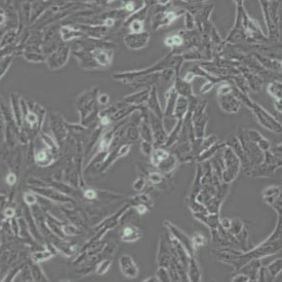

细胞中文名称:SKNSH人神经母细胞瘤细胞(带STR鉴定)

| 名称 | SK-N-SH (人神经母细胞瘤细胞) (STR鉴定正确) |

| 细胞形态 | 上皮细胞样 |

| 背景描述 | SK-N-SH细胞是由J·L·Bieder建系,它与SK-N-MC细胞所不同的是倍增时间较长,且多巴胺-β-羟基酶水平较高。SK-N-SH细胞在细胞介导的细胞毒性试验中用作靶细胞系。 |